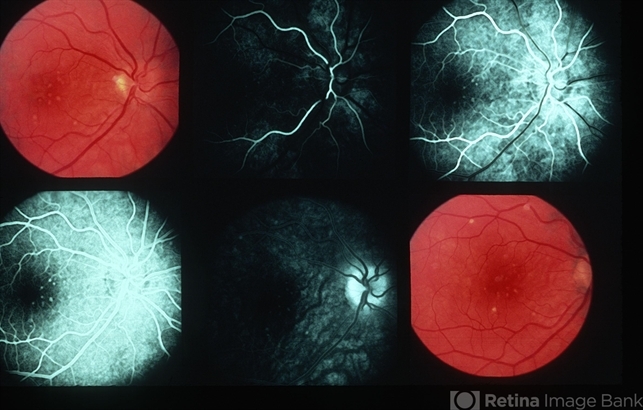

- Multiple Evanescent White Dot Syndrome (MEWDS)

- III MEWDS.